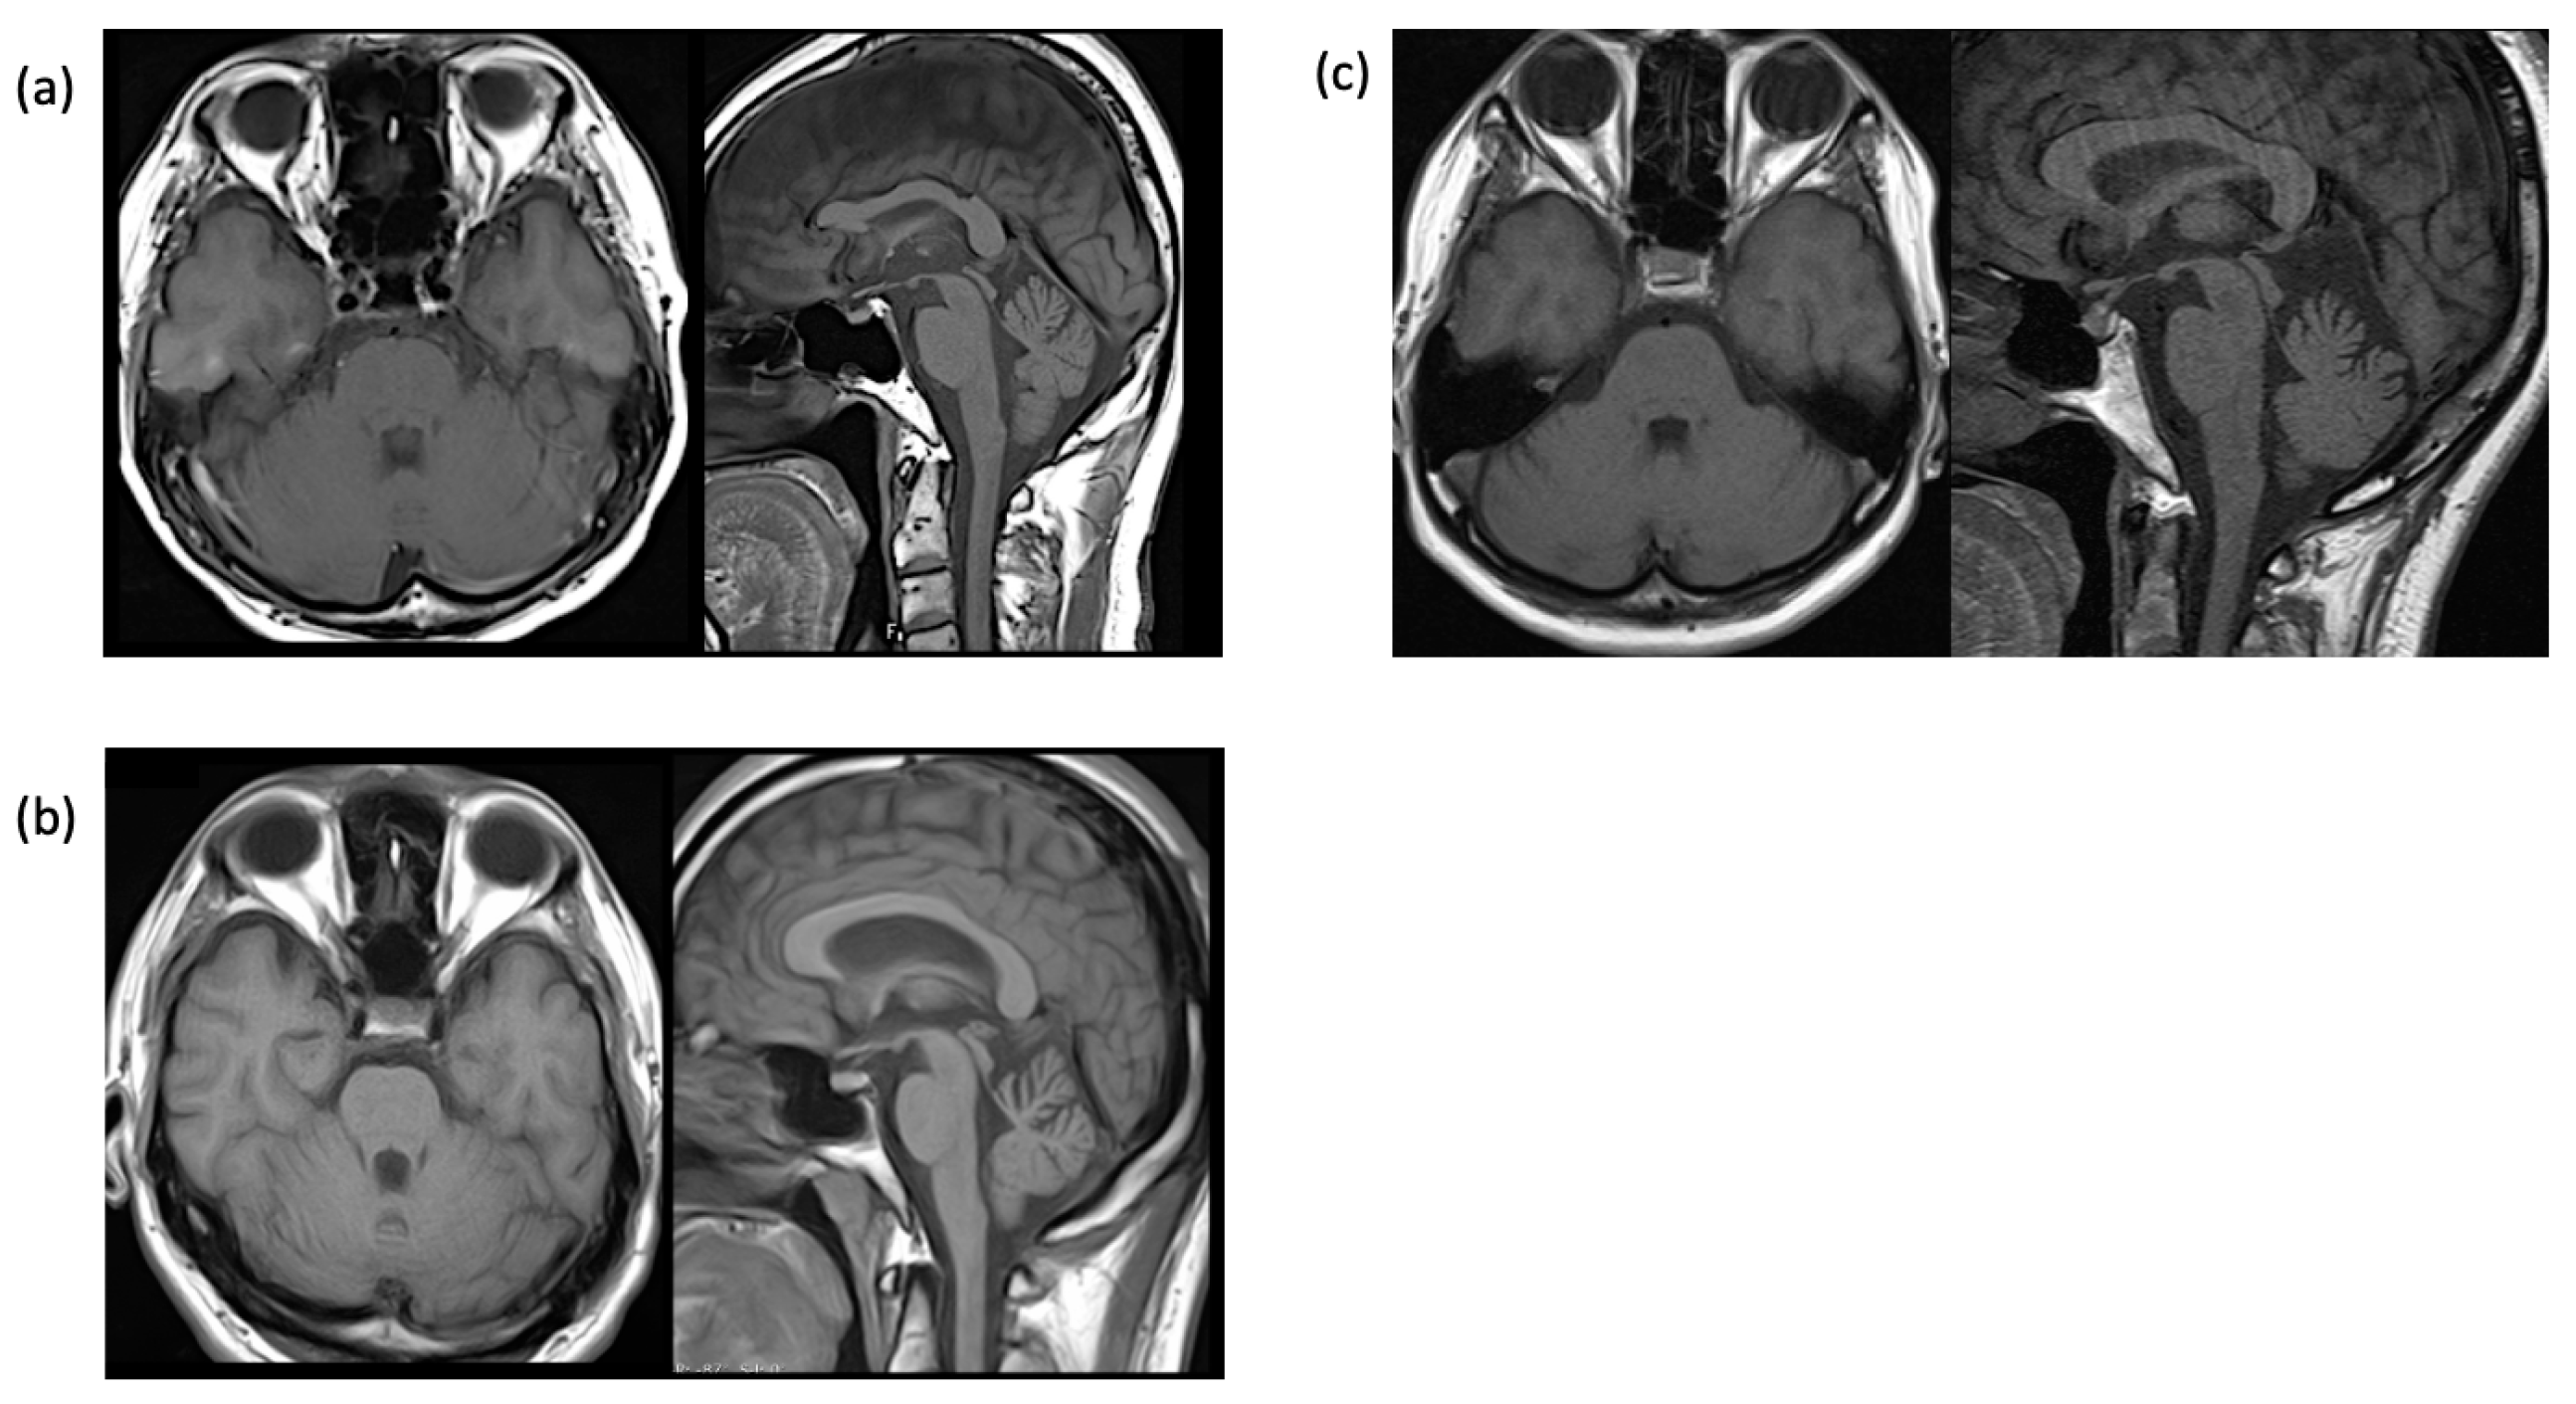

| Brain MRI: cerebellar atrophy | +− | + | + |